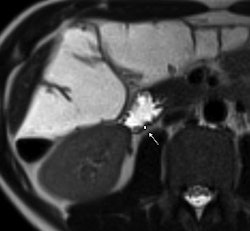

| 1.5-tesla MR images show a portion of the duodenum wall in a patient with untreated celiac disease (above), a patient with treated celiac disease (below), and a healthy patient (bottom). The images show no significant differences in duodenal wall thickness (arrow). |

Their analysis found that a mean maximum enhancement of the duodenal wall was 229.1 ± 46.4 in untreated patients with celiac disease, 109.8 ± 27.8 in treated patients with celiac disease, and 94.7 ± 17.9 in control subjects.

"This MR parameter was significantly higher in patients with untreated celiac disease than in patients with treated celiac disease and control subjects," the authors wrote, while maximum enhancement did not significantly differ between the patients with treated celiac disease and controls.

The researchers also found that duodenal wall thickness did not significantly differ between patients with celiac disease who were not treated for the condition, patients with celiac disease who were treated, and healthy control subjects.